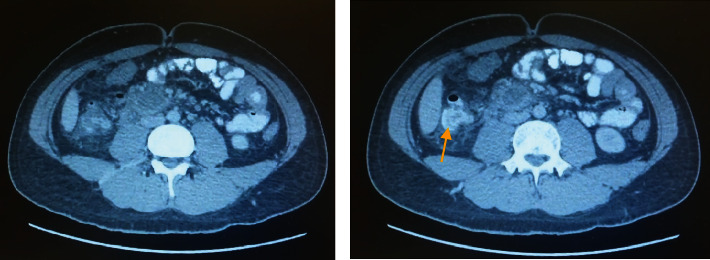

Multiple types of fistulas associated with the appendix have been reported; however, duodenal fistula resulting from perforated acute appendicitis has only been documented in one previous case. In this report, we present the case of an 18-year-old male patient who was diagnosed to have a complicated appendicitis in its normal position with abscess formation. He was started on IV antibiotics and underwent a CT-guided drainage of the abscess with drain placement. Two days later due to biliary output from the drain, CT fistulography and diagnostic laparoscopy were performed that revealed the presence of a duodenal fistula. The potential for duodenal fistula formation in patients with complicated appendicitis must always be taken into consideration. Consequently, it is crucial to establish an appropriate management plan aimed at preventing additional serious complications arising from duodenal perforation.

与阑尾相关的瘘管有多种类型,但因急性阑尾炎穿孔而导致十二指肠瘘的病例仅有一例。在本报告中,我们介绍了一名 18 岁男性患者的病例,他被诊断为复杂性阑尾炎,阑尾位置正常,并有脓肿形成。他开始静脉注射抗生素,并在 CT 引导下进行了脓肿引流术,同时放置了引流管。两天后,由于引流管排出胆汁,医生为他进行了CT瘘管造影和诊断性腹腔镜检查,结果显示存在十二指肠瘘。必须始终考虑到复杂性阑尾炎患者十二指肠瘘形成的可能性。因此,制定适当的管理计划以防止十二指肠穿孔引起其他严重并发症至关重要。